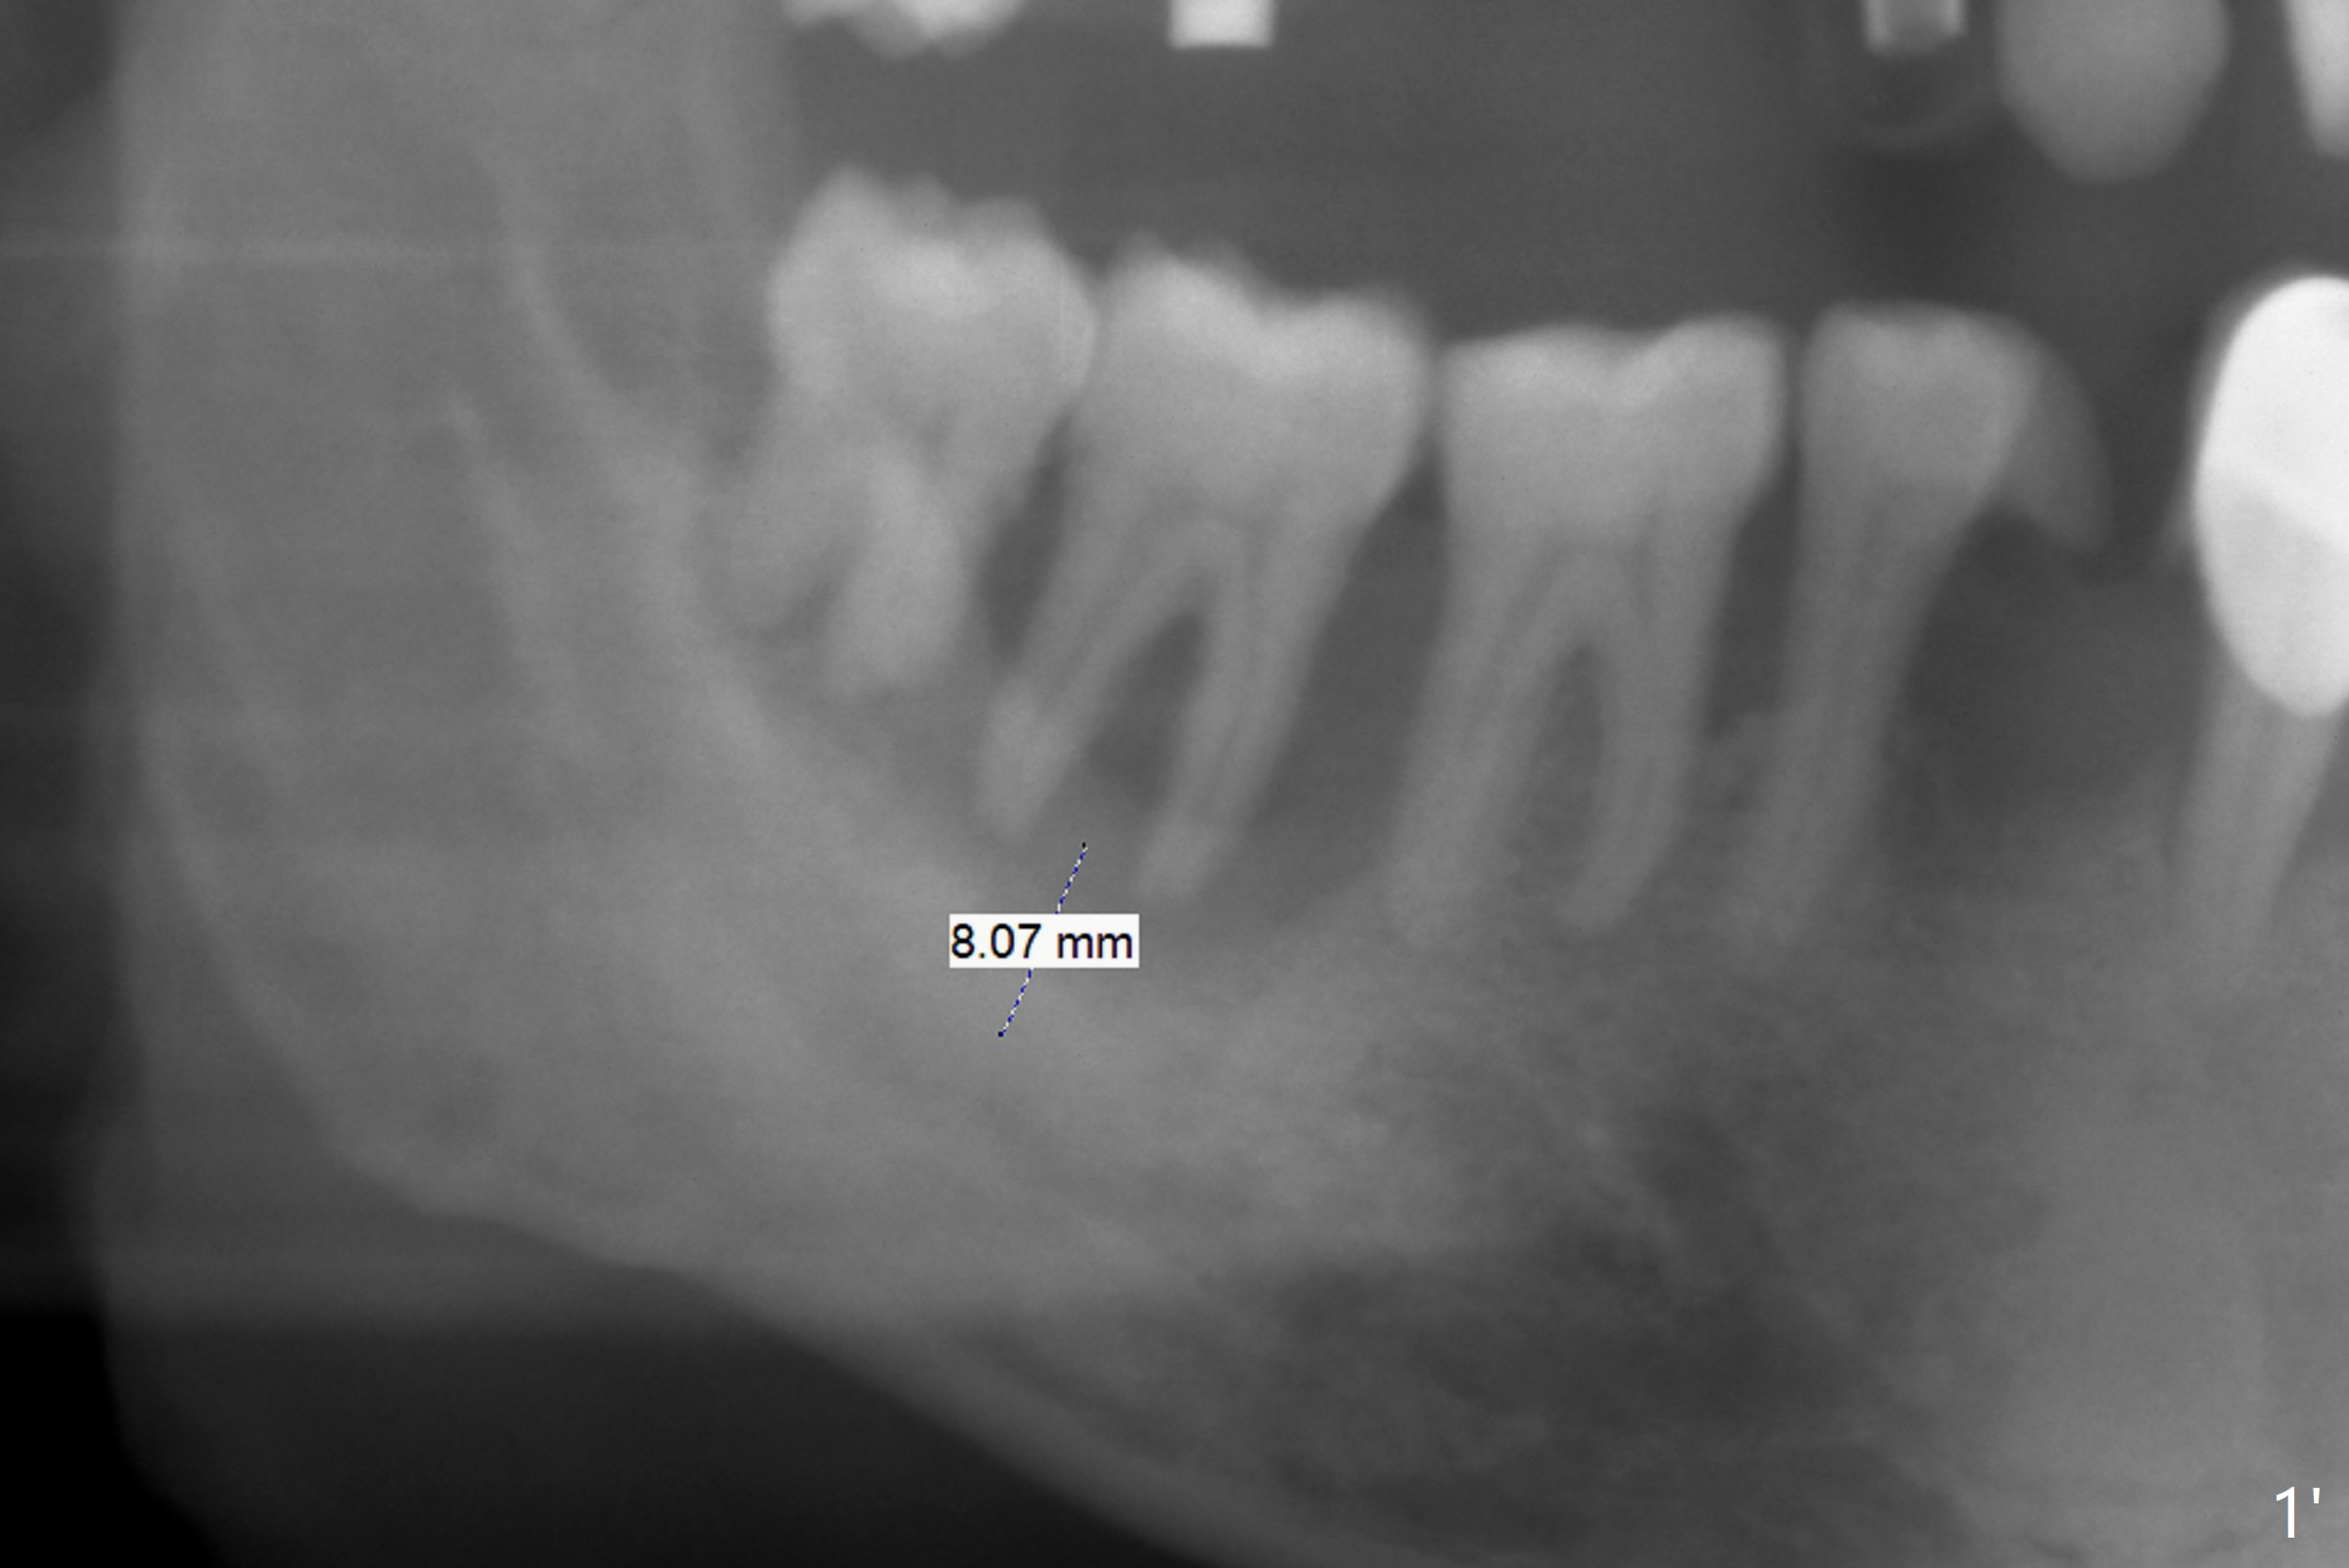

After having upper implants placed (9-11, 15 UR), a 46-year-old man requests taking care of the loose tooth at #31 and the missing tooth #28 next (Fig.1).  Bone height is limited at #31 (Fig.2); if hemorrhage and pain are controllable, an extra wide Bicon implant will be placed.  In the posterior region with unfavorable implant crown ratio, there is less likelihood to separate Bicon abutment from its implant because of friction mechanism.   But 3-5 mm stoppers and drills are from another implant system (regular and wide kits).  CT may be taken intraop if needed.  PRF membranes will be used to close the large socket opening with a hole for a healing abutment penetration if instructed.  Autoclave a needle with endo syringe to inject PRF liquid into the tissue to facilitate tissue healing.

Limited Bone Height